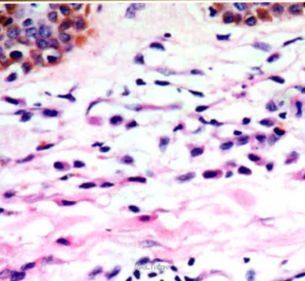

皮肤科检查:躯干、四肢泛发粟粒至黄豆大圆形或椭圆形暗红色斑丘疹.散在分布.以躯干为主.Darier征阳性。实验室及辅助检查:未见异常。皮损组织病理检查:表皮正常.真皮内可见单一核细胞弥漫浸润,细胞中等大小、形态一致,核呈圆形、卵圆形或肾形,位于细胞中央,胞质淡染或透明,核分裂象偶见;真皮浅层尚可见灶性淋巴细胞浸润:吉姆萨染色可见部分细胞内有紫红色嗜异染颗粒。

诊断:皮肤肥大细胞增生症。治疗:口服左西替利嗪5 mg Qd及复方甘草酸苷50 mg tid,治疗15 d后观察有一定疗效。